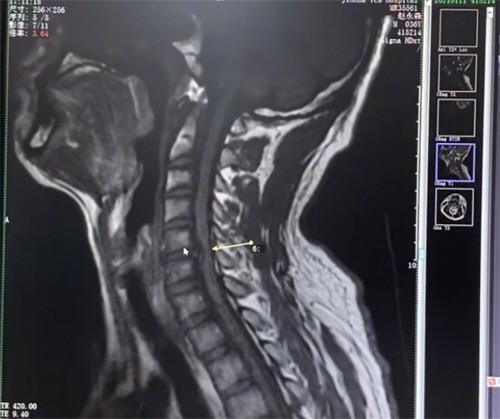

头颅MRI检查显示,张先生右侧小脑出现大面积梗死灶,伴随眼球震颤等典型症状。进一步颈部CTA检查发现,其右侧椎动脉V2段存在夹层样改变,血管壁因外力挤压出现撕裂,血液渗入形成血肿,导致血管狭窄并产生血栓。血栓脱落后随血流冲入颅内,最终堵塞小脑供血动脉。